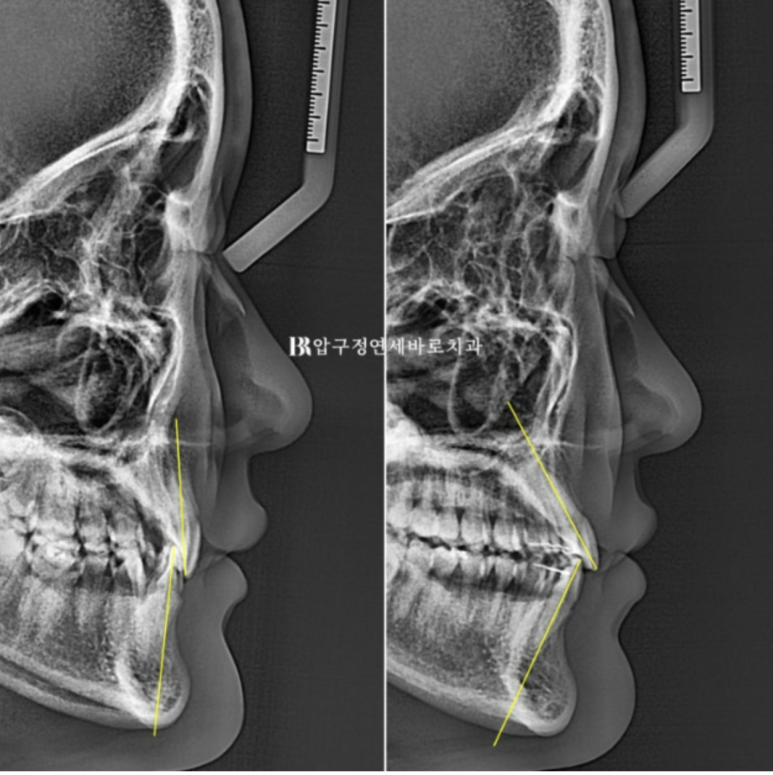

앞니가 뒤로 기울어져 있으니 입술에 볼륨감이 부족하여 얇아 보입니다.

환자분은 주걱턱처럼 아래턱 끝이 나와보여서 개선을 원하였으나

교정으로 턱끝은 움직일 수 없습니다.

Q. 옥니 교정하면 주걱턱도 들어가나요?

A. 턱뼈 자체는 교정으로 이동하지 않지만, 입술 볼륨이 회복되면서 상대적으로 턱끝이 덜 돌출되어 보이는 효과가 있습니다.

이 점 말씀드리고 치료에 들어갔습니다.

옥니 교정으로 입술에 입체감만 살아나도 턱끝이 상대적으로 덜 나와 보입니다.

마치 무턱 돌출입 환자에서 교정 후 호두턱이 풀리고 입술 돌출이 개선이 되면 마치 상대적으로 턱끝이 나와보이는 것과 비슷합니다.

치아는 철저히 원근법을 따릅니다.

입매는 항상 얼굴 전체와의 조화 그리고 코나 턱끝 부위와의 조화가 중요합니다.

교정으로 아래턱이 뒤로 들어간 것은 아니지만

입술 볼륨이 회복이 되면 주걱턱으로 보이던 것도 개선이 됩니다.